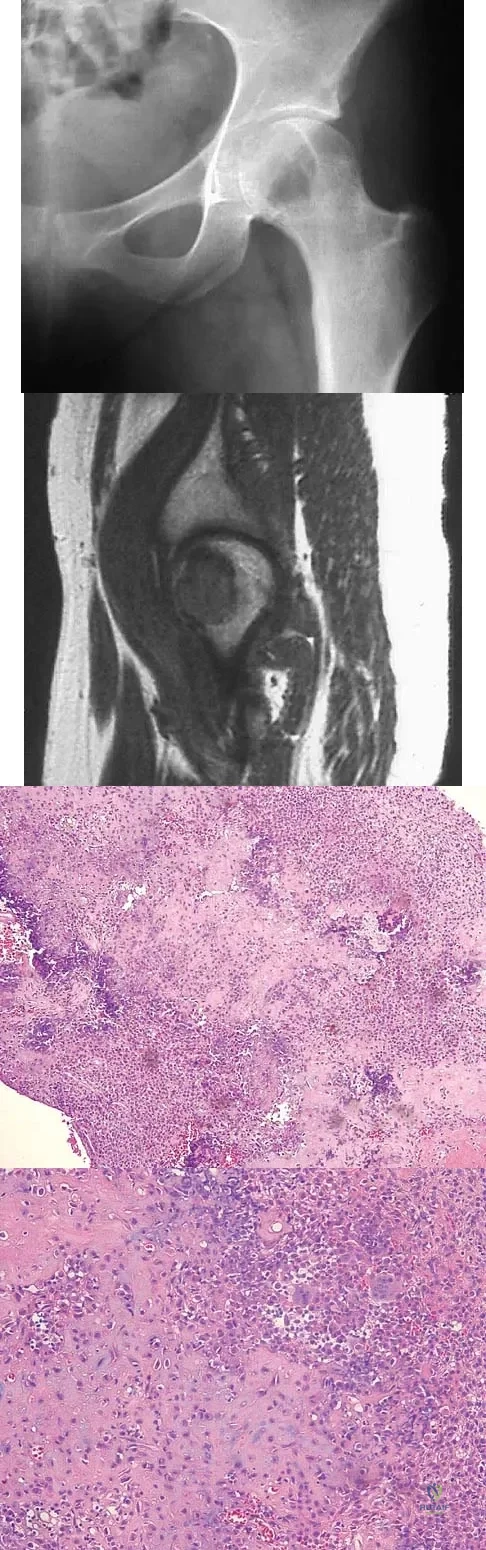

A 16-year-old girl has had pain in the left groin for the past 4 months. She notes that the pain is worse at night; however, she denies any history of trauma and has no constitutional symptoms. There is no history of steroid or alcohol use. Examination reveals pain in the left groin with rotation of the hip. There is no associated soft-tissue mass. A radiograph and MRI scan are shown in Figures 32a and 32b, and biopsy specimens are shown in Figures 32c and 32d. What is the most likely diagnosis?

Explanation